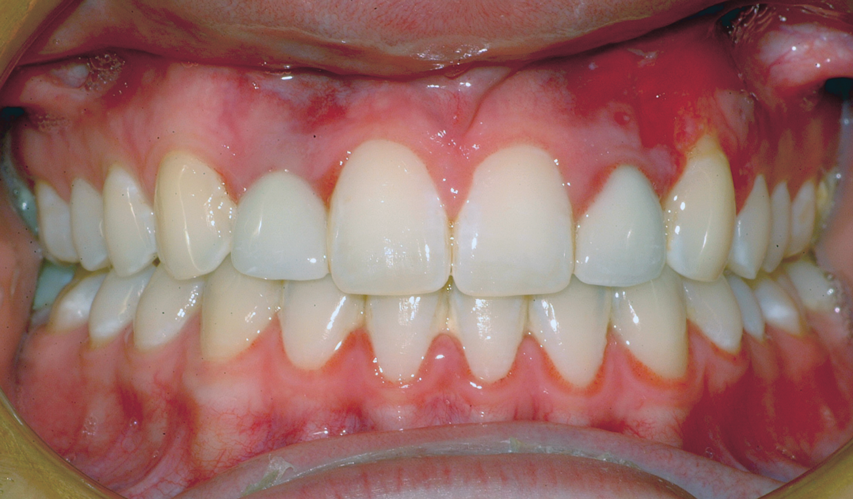

A third risk of using an implant to replace a missing lateral incisor is the continued vertical growth of the alveolar bone and eruption of the teeth adjacent to the implant.9,10 Traditionally, it has been taught that an implant can be safely placed when alveolar bone growth is confirmed complete with serial radiographs. However, numerous studies call that rule into question.11-16 Bernard et al evaluated vertical changes in teeth adjacent to implants in a young group of patients (15.5 to 21 years) and in a mature group (40 to 55 years), over a mean time of 4.2 years.17 In the young group, infraocclusion of the implant crowns ranged from 0.1 mm to 1.65 mm, while in the mature group the infraocclusion of the implant crowns ranged from 0.12 mm to 1.86 mm. An example of infraocclusion that occurred in a young implant patient over time is depicted in Figure 3 and Figure 4. Based on classic literature as cited here, it seems prudent to delay the placement of implants in high-risk areas, such as the maxillary lateral incisor region, for as long as possible or perhaps avoid it altogether.

Fig 3. Implants were placed in a 20-year-old female patient in the Nos. 7 and 11 sites with a pontic replacing No. 10.

Figure 3

Fig 4. A 15-year postoperative photograph of the patient in Fig 3 illustrates the significant infraocclusion of the implants compared to the natural teeth. Also, note the blue tissue discoloration over implants Nos. 7 and 11.

Figure 4